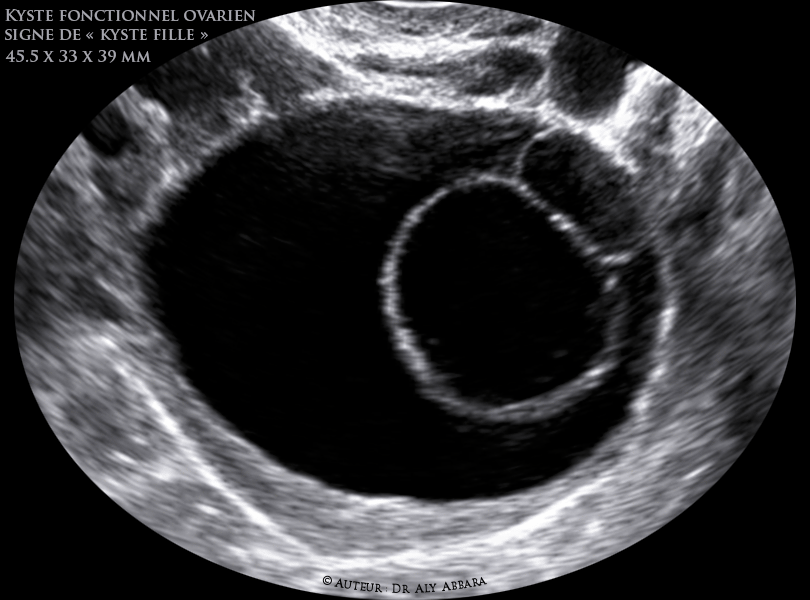

Kyste ovarien fonctionnel Signe de kyste fille -(Daughter cyst sign)

Signe de « kyste fille » (Daughter cyst sign)

Kyste ovarien fonctionnel complexe, composé d'une formation kystique mesurant 45,5 x 33 x 39 mm, contenant deux formations kystiques plus petites (deux filles)

ou deux follicules de De Graaf in égaux en volume.